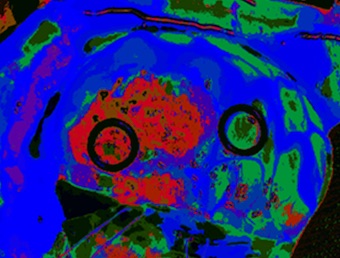

HELICoiD, a collaborative project co-funded by the European Union under its 7th Framework Programme, was created to investigate the use of hyperspectral imaging in cancer diagnosis, in particular the real-time discrimination between healthy and malignant tissues in brain cancer. The project, named for HypErspectraL Imaging Cancer Detection, aimed to model how cancer affects the hyperspectral signature of tissues, assisting clinicians in making a traditionally difficult distinction.

The HELICoiD demonstrator included two hyperspectral cameras, one in the 400 to 1000 nm range and the second covering 900 to 1700 nm. Using a dataset of hyperspectral images from healthy and cancerous tissue, an algorithm was trained to detect differences in the spectral signature using machine learning techniques, and then applied to images acquired during surgery.

In three data acquisition campaigns carried out in Spain and the UK, the HELICoiD demonstrator and subsequent algorithm analysis provided a very good correlation between the real positions of the tumors seen by clinicians and the automatic predictions of the tumor margins made by the system.